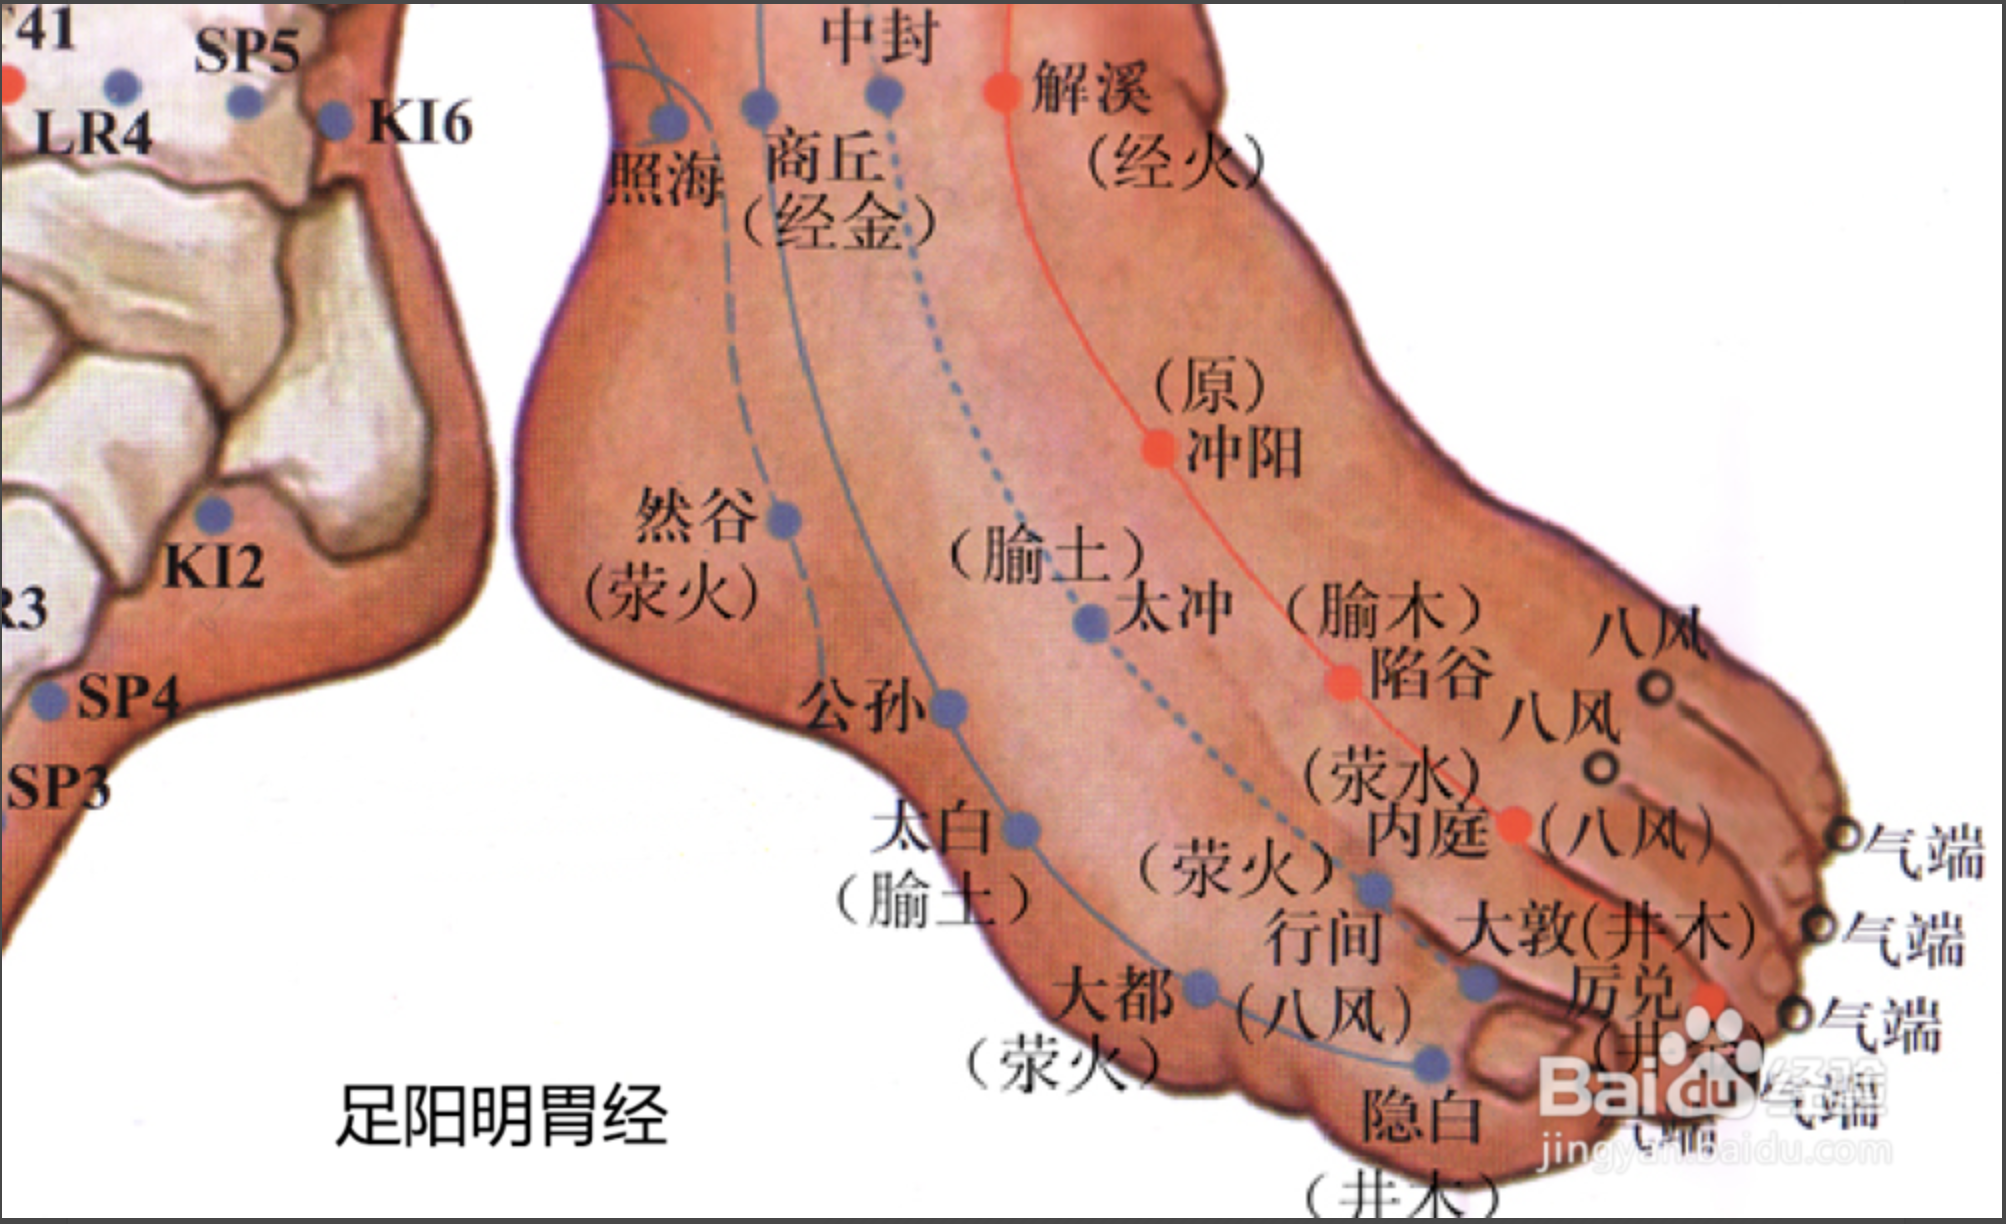

【(三)足阳明胃经(图10-21-1)】

图 10-21-1 足阳明胃经循行及常用腧穴

1、时辰 辰时 7 ~ 9

2、歌诀 四十五穴足阳明,承泣四白巨髎(liáo)经,地仓大迎下颊车,下关头维对人迎,水突气舍连缺盆,气户库房屋翳寻,膺窗乳中下乳根,不容承满出梁门,关门太乙滑肉起,天枢外陵大巨里,水道归来达气冲,髀关伏兔走阴市,梁丘犊鼻足三里,上巨虚连条口底,下巨虚下有丰隆,解溪冲阳陷谷同,内庭厉兑阳明穴,大趾次趾之端终。

3、经脉循行 起于鼻翼两侧(迎香),上行到鼻根部与足太阳经交会,向下沿鼻外侧进入上齿龈内,回出环绕口唇,向下交会于颏(kē)唇沟承浆处,再向后沿口腮后下方,出于下颌(hé)大迎处沿下颌角颊车,上行耳前,经上关,沿发际,到达前额(前庭)。

面部支脉:从大迎前下走人迎,沿着喉咙,进入缺盆部,向下过膈,属于胃,联络脾脏。

缺盆部直行的脉:经乳头,向下夹脐旁,进入少腹两侧气冲;

胃下口部支脉:沿着腹里向下到气冲会合,再由此下行至髀(bì)关,直抵伏兔部,下至膝盖,沿胫骨外侧前缘,下经足跗;进入第二足趾外侧端(厉兑)。

胫部支脉:从膝下 3 寸(足三里)处分出进入足中趾外侧端。

足跗部支脉:从跗上分出,进入足大趾内侧端(隐白)与足太阴脾经相接。

4、主要病候 肠鸣腹胀、水肿、胃痛、呕吐或消谷善饥、口渴、咽喉肿痛、鼻衄、胸部及膝髌(bìn)等本经循行部位疼痛、热病、发狂等。

5、主治概要 主治胃肠病、头面、目鼻、口齿痛、神志病及经脉循行部位的其他病证。

厉兑

【定位】 在足第 2 趾末节外侧,距趾甲角 0.1 寸。

【主治】 鼻衄,齿痛,咽喉肿痛,腹胀,热病,多梦,癫狂。

【配伍】 配内关、神门治多梦。

【刺灸法】 浅刺 0.1 寸。

【附注】 足阳明经所出为“井”。